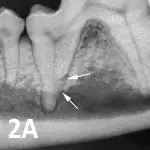

Featured Image

Figure 2A

Type 1 resorption. Arrows point to distal root resorption lacuna with discernible periodontal ligament space.

Type 1: There is alveolar bone loss adjacent to well-defined areas of tooth resorption. The lesion appears radiographically discrete and unaffected areas of the root appear normal. Normal periodontal ligament space is maintained at other areas of the tooth (See Figure 2A). If the lesion extends into the oral cavity, the tooth should be extracted.